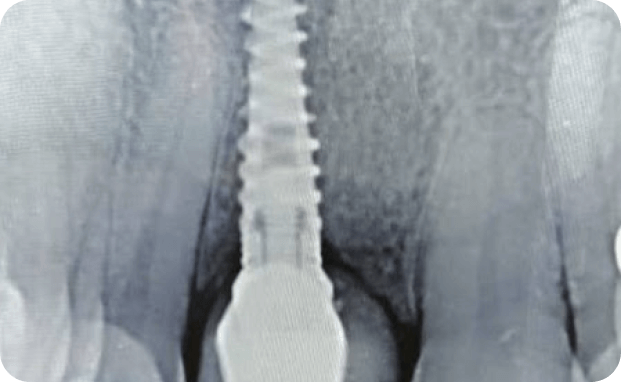

Casos

Instalaciones oral group Instalaciones oral group Instalaciones oral group Instalaciones oral group Instalaciones oral group Instalaciones oral group Instalaciones oral group